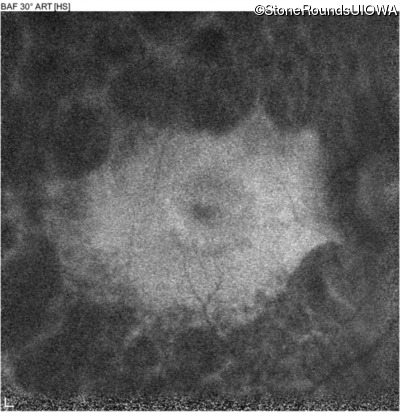

Infrared Fundus Photograph - Right - 20/50

Exemplar

Infrared Fundus Photograph - Left - 20/50